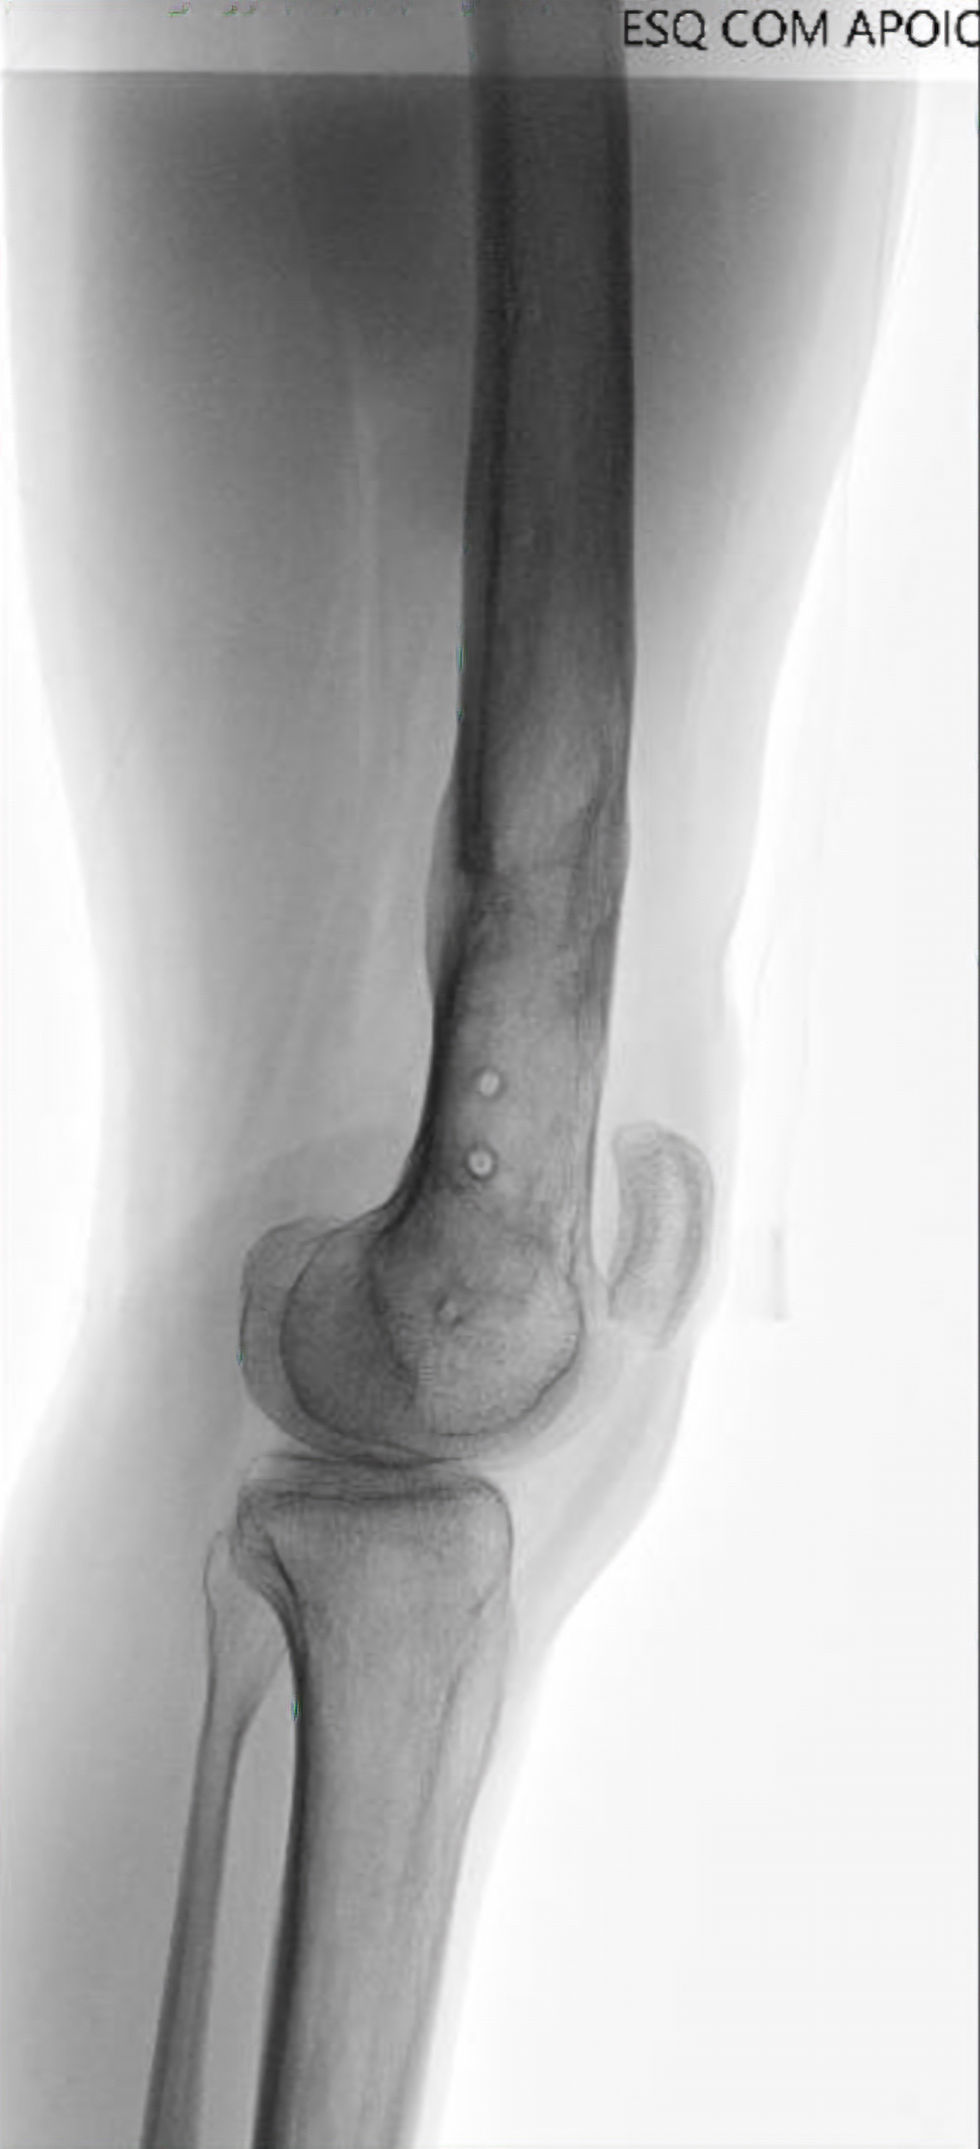

O que é a técnica ILN ?

O alongamento ósseo com haste motorizada representa uma evolução do método de Ilizarov — aplicando os mesmos princípios biológicos, mas com tecnologia interna e conforto superior.

O alongamento ósseo com haste motorizada intramedular é uma técnica moderna de reconstrução ortopédica que permite aumentar o comprimento do osso (geralmente fêmur ou tíbia) de forma interna, sem fixador externo visível.

A haste é implantada dentro do canal medular do osso e possui um mecanismo eletrônico motorizado, controlado por um sistema externo por radiofrequência (RF) ou ímã, que promove o alongamento progressivo e preciso.

Princípio de funcionamento

O método de Ilizarov continua aqui: osteotomia controlada + distração gradual → formação de osso novo (regenerado) no espaço criado.

A diferença é o mecanismo interno de distração, que substitui o uso de fixadores externos.

Passo a passo do ILN

Veja as etapas 1️⃣ Planejamento pré-operatório - Radiografias panorâmicas e tomografia para medir o membro e planejar o eixo. - Escolha do modelo e comprimento da haste. - Definição da zona da osteotomia e da meta de alongamento. 2️⃣ Cirurgia - Realizada sob anestesia, com o paciente em decúbito dorsal. - Introdução da haste motorizada no canal medular após fresagem. - Osteotomia minimamente invasiva (metafisária, preservando o periósteo). - Fixação da haste com parafusos proximais e distais. - Teste de funcionamento do motor interno com o controle externo. 3️⃣ Pós-operatório imediato - Fisioterapia e deambulação parcial iniciadas precocemente. - O paciente realiza o alongamento sob orientação médica. 4️⃣ Fase de distração (alongamento) - Início após 5–7 dias de latência. - Ativação com controle externo: 0,25 mm × 4/dia = 1 mm/dia. - Radiografias semanais para acompanhar regenerado e alinhamento. - Duração: cerca de 10 dias por centímetro desejado (ex.: 5 cm → ~50 dias). 5️⃣ Fase de consolidação - Interrompe-se a distração após atingir o comprimento planejado. - O osso novo se mineraliza gradualmente. - Carga parcial progressiva conforme densidade radiográfica. - Radiografias mensais até consolidação (≈ 1–2 meses/cm alongado). 6️⃣ Reabilitação - Fisioterapia diária: mobilidade articular, força e marcha. - Carga total e retorno às atividades geralmente 6 e 12 meses. 7️⃣ Retirada da haste Após consolidação completa e estabilidade do comprimento. Procedimento eletivo, minimamente invasivo, sob anestesia.